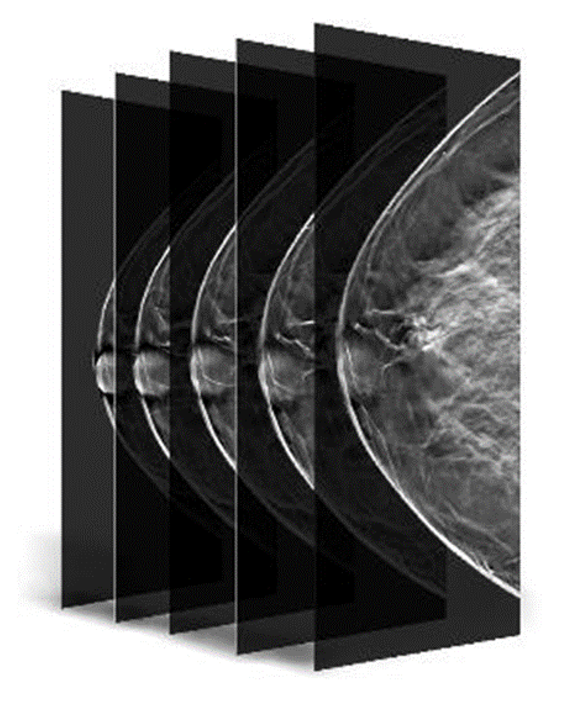

Gelişmiş 3D Tomosentez Teknolojisi

Hologic Selenia® Dimensions, FDA onaylı Genius™ 3D tomosentez teknolojisi ile meme dokusunu yüksek çözünürlükte katman katman tarar. Bu ileri teknoloji, geleneksel 2D mamografiye kıyasla meme kanserini %20 ile %65 arasında daha yüksek oranda tespit ederek erken teşhiste önemli bir avantaj sunar. Klinik çalışmalar, bu sistemin yalancı pozitif çağrı oranlarını %40’a kadar azaltarak gereksiz biyopsi sayısının düşürülmesini sağladığını ortaya koymaktadır. Özellikle yoğun ve karmaşık meme yapısına sahip hastalarda, lezyonların daha net görünmesini mümkün kılarak radyologların tanı güvenilirliğini artırır.

Clarity HD™ teknolojisi, Hologic’in dijital mamografi sistemlerinde yer alan yüksek çözünürlüklü 3D görüntüleme teknolojisidir. Bu sistem, meme dokusunu 70 mikron çözünürlükle katman katman tarayarak olağanüstü netlikte tomosentez görüntüleri sunar. Sonuç: daha doğru tanılar, daha az tekrar çekim ve daha güvenli tarama kararları.

Özellikle yoğun meme dokusuna sahip hastalarda, Clarity HD, dokuların üst üste binmesini önleyerek küçük kitleler, gizli kalsifikasyonlar ve diğer anormalliklerin (örneğin spiküler lezyonlar veya distorsiyonlar) daha görünür hale gelmesini sağlar. Bu da erken evre meme kanserinin tespiti açısından kritik öneme sahiptir. Geleneksel 2D sistemlerle karşılaştırıldığında, Clarity HD ile elde edilen görüntü netliği %50’ye kadar artarken, belirsiz tanılar nedeniyle istenen ileri görüntüleme oranları %40’a kadar azalmaktadır.